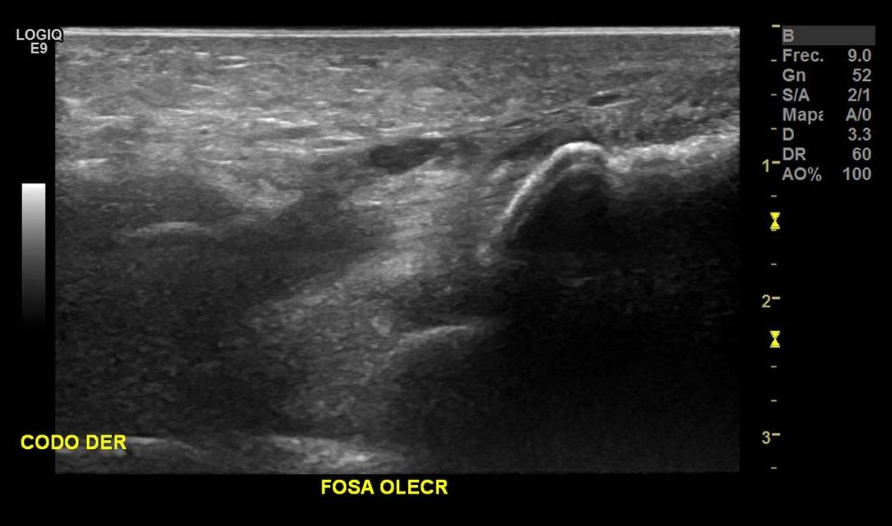

Paciente con antecedentes de fractura avulsiva del olecranon en codo derecho de 1 día de evolución, se presenta con hematoma y aumento de volumen difuso en articulación. Examen se solicita para conocer el porcentaje de compromiso del tendón tricipital.

Edema celular subcutáneo en región medial, lateral y posterior de codo der, con señal Doppler.

No se observan fibras del tendón del tríceps a nivel insercional, con fragmento óseo avulsivo en tercio medio del tendón del tríceps, correspondiente a rotura total.

Hallazgos: Tendón tricipital no visualizado en el tercio distal, en el contexto de rotura completa, con gap de 43 mm y fragmento óseo avulsivo en su espesor en el tercio medio, mide 9 mm. Se identificaron extensos cambios inflamatorios a este nivel y aumento de señal al estudio Doppler Color.

Significativo edema del tejido celular subcutáneo medial, lateral y posterior, con aumento de señal al estudio Doppler Color.